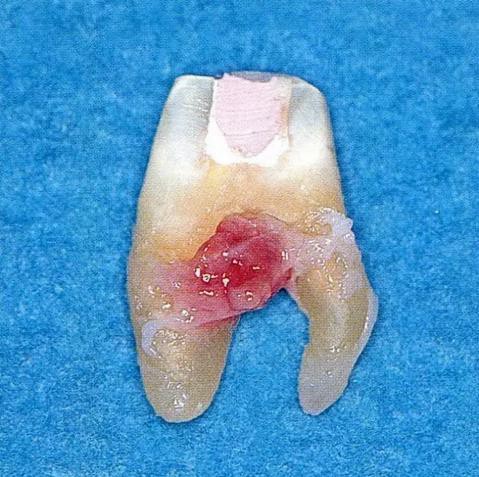

▼圖6-1 下頜第一后磨牙的頰舌間存在III度的根分叉病變,預(yù)在進行牙根分割后保留遠中根。

▼圖6-2 中下頜第一后磨牙雖然切除了一半,但是遠中根也有2根分根,所以不得已拔除(被拔除遠中根的近中面觀察)。